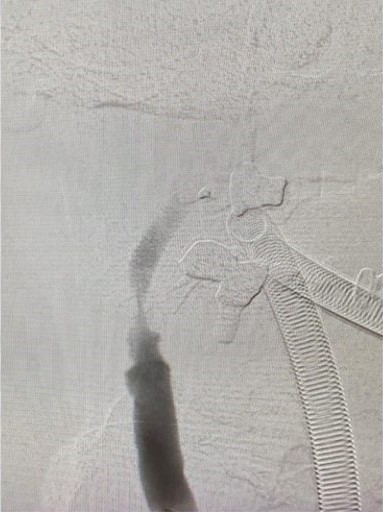

羅先生被送往私家醫院的第一步是進行緊急磁力共振造影,報告顯示羅先生右邊頸和腦部血管大動脈全部都被血栓堵塞着,右邊大腦缺血水腫,導致左邊手腳冇力和神智半昏迷。經過腦血管外科醫生的診斷和急救,在全身麻醉下,醫生使用尤如髪絲微細的導管,經過病人右邊大腿的腹股溝的大動脈而入,導管再經過腹部和胸腔的大動脈一直向上,遊走到病人右邊的頸和腦部血管大動脈,進行機械式血栓吸取內血管治療急救。

手術成功 患者手腳活動能力恢復

經過1小時的血管急救,所有血栓都被移除,羅先生的右頸和腦部血管都給順利打通,腦部缺血情況立即得到改善。血栓被吸取後,腦血管外科醫生發現羅先生的右頸內動脈有嚴重血管狹窄的情況,這個狹窄就是羅先生中風的主要原因。醫生因此植入血管支架來重新擴張狹窄的血管,以防止羅先生將來中風復發。全身麻醉清醒後,羅先生的大腦意識和手腳活動能力即時好轉,他其後再被送回另一間公立醫院繼續康復治療。